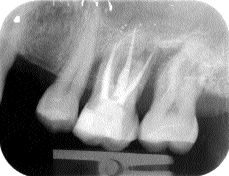

By Gary D. Glassman, DDS, FRCD(C), Kenneth S. Serota, MMSc, DDS, and Frederic Barnett, DMD Dentistry is dangerously close to becoming a runaway train. Techno-products abound; they are the engines that drive the service mix. Unfortunately in far too many cases they are an application in search of a situation. The biologic objectives are often … Read more